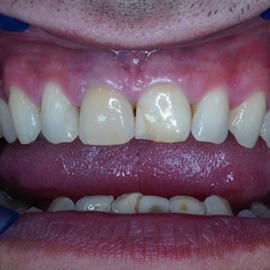

Wybielanie obejmujące pojedyncze zęby jest dość często spotykane. Najczęstszą przyczyną dyskoloracji zęba jest obumarcie miazgi i brak następowego poprawnego leczenia kanałowego, lub leczenie nieprawidłowe. Czasami udaje się przeprowadzić proces wybielania, który jest zadowalający dla pacjenta, a czasami w oparciu o uzyskany wynik można przeprowadzić leczenie protetyczne np. koroną lub licówką całoceramiczną.

Trzeba jednak uważać, ponieważ nieumiejętnie przeprowadzone wybielanie może być przyczyną resorpcji wewnętrznej i może sie skończyć utratą całego zęba...juz wybielonego. Poniżej zdjęcia przed i po leczeniu mikrochirurgicznym resorpcji.